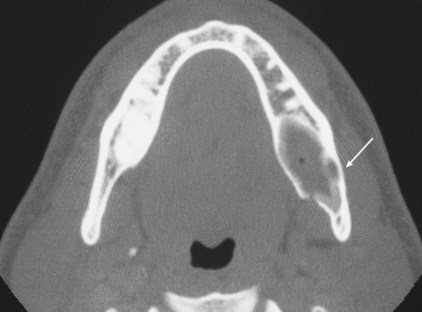

• CT scans of the mandible:

• Generally are not optimal for routine screening:

• But may be considered in certain circumstances:

• Such as primary tumors of the mandible and lesions where soft tissue extension from tumors involving the ascending ramus of the mandible is suspected (Figure)

• A computerized tomogram of the oral cavity and neck:

• Is the standard initial radiographic study for assessment of locoregional extent of the tumor

• It allows comprehensive evaluation of neck nodes and also the relationship of the primary tumor to adjoining bone:

• Especially in situations such as primary tumors of the mandible and lesions where soft-tissue extension from tumors involving the ascending ramus of the mandible is suspected